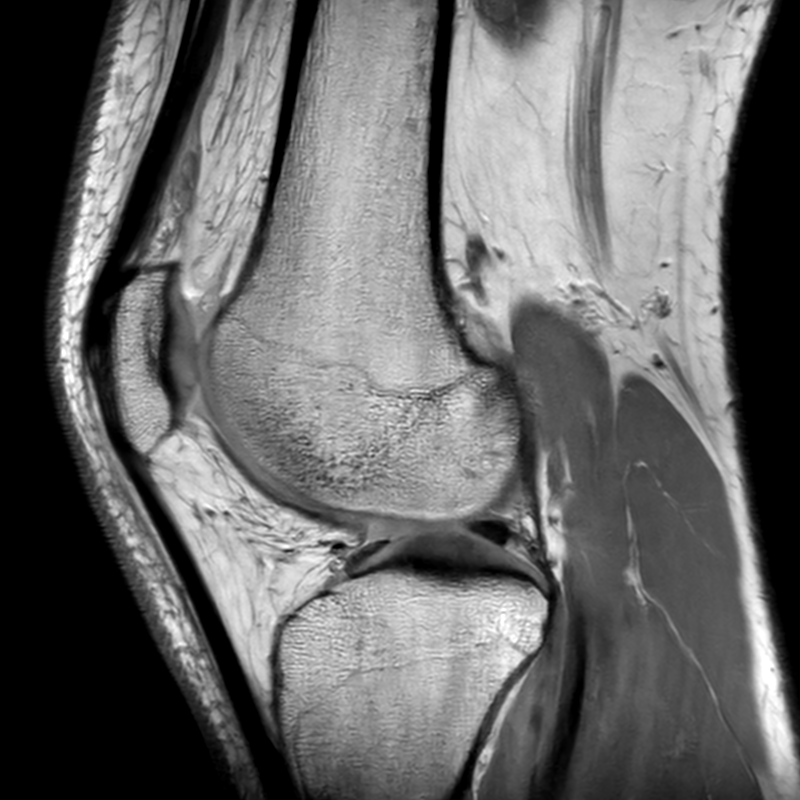

Een paar weken geleden begon ik pijn te voelen aan beide knieën, vooral tijdens het lopen. Omdat de pijn na een aantal weken zelfs in rust niet meer verdween, besloot ik een MRI te laten nemen.

De resultaten waren duidelijk: ik heb kraakbeenschade. Vooral het kraakbeen op mijn knieschijf is zwaar aangetast — op sommige plekken zelfs volledig verdwenen (graad 4, voor de kenners). Dat zorgt voor pijn bij zowat alles wat ik doe: lopen, trappen nemen, hurken en — jawel — wedstrijden lopen.

Gelukkig is er ook goed nieuws: mijn meniscus, kruisbanden, pezen en spieren zijn allemaal in uitstekende staat. Alleen dat vervelende kraakbeen gooit nu roet in het eten.